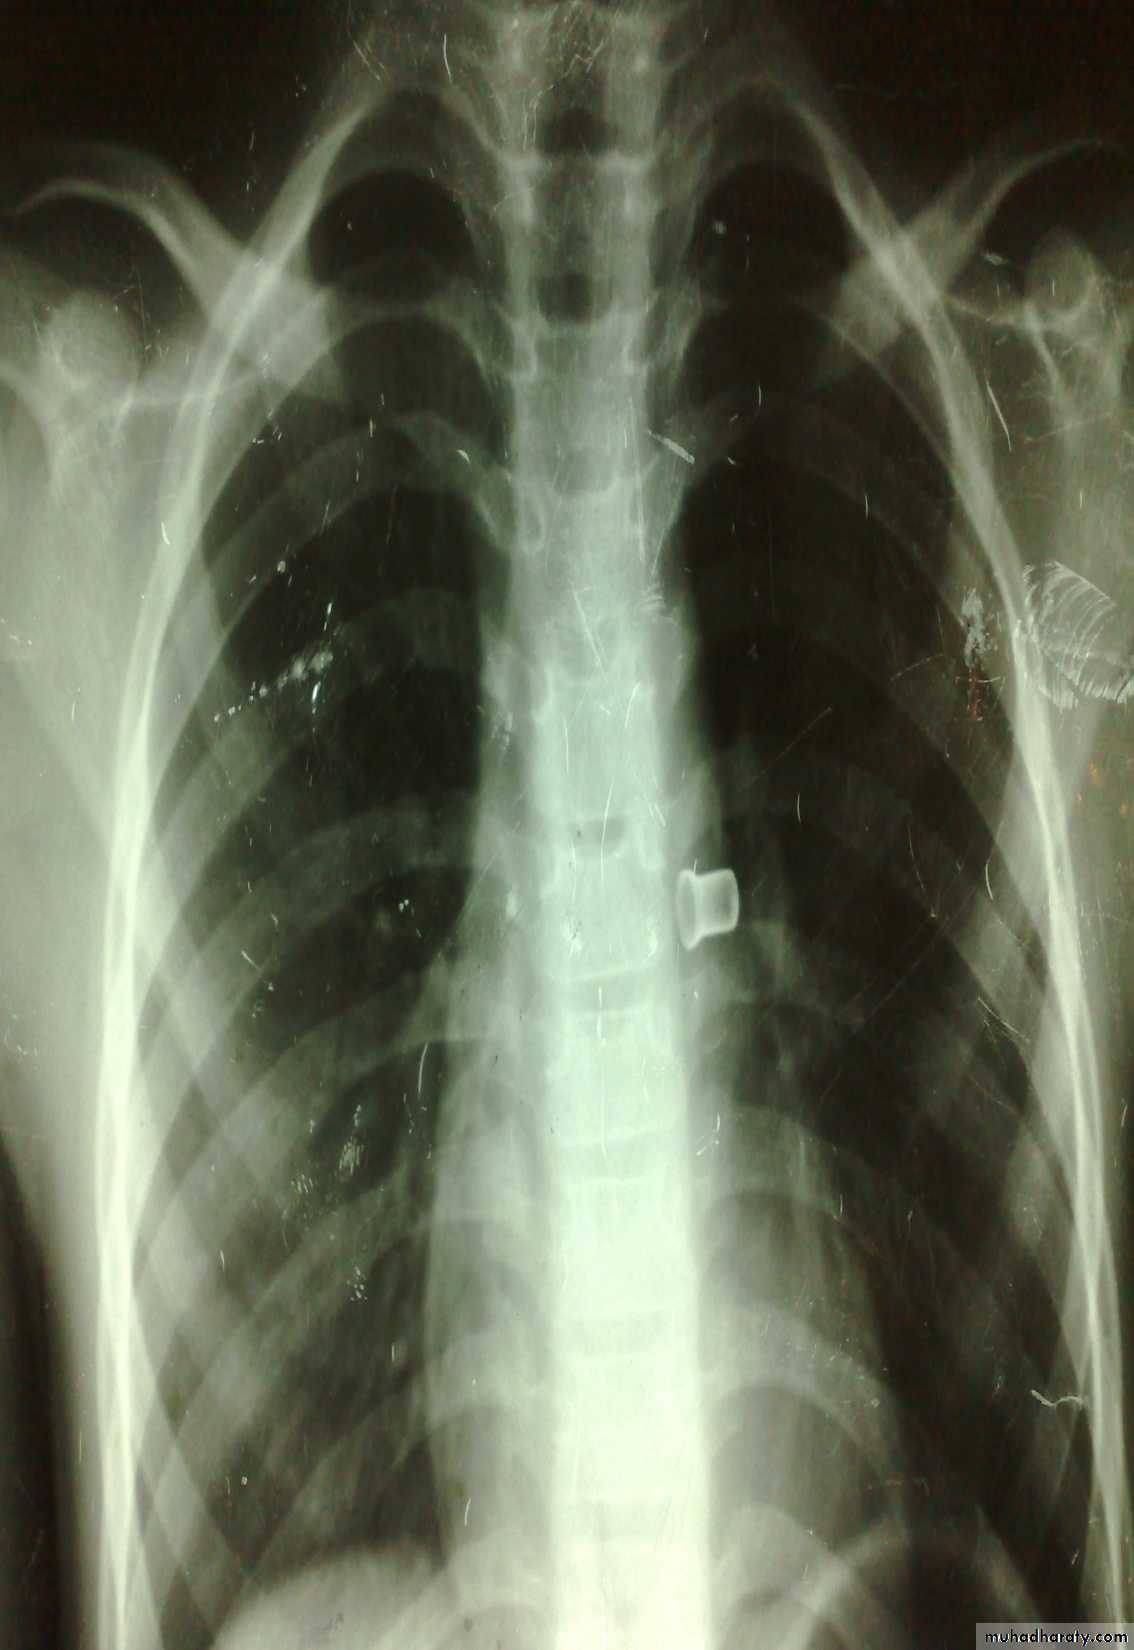

Esophageal F.B

Clinically:salivation +no strioder1st F.b in Lt main bronchus removed by bronchoscopy